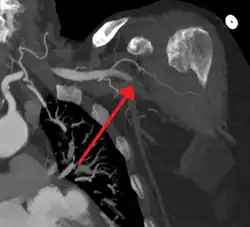

Acute occlusion of the axillary artery resulting in an ischemic limb as seen on CT angiography

Once signs and symptoms of acute limb ischemia are identified, the cause and location of the occlusion and its severity need to be addressed. A clinical pulse examination can be done to detect the location of the occlusion by finding the area where the pulse is detected until the area where the pulse disappears. The skin temperature would also be colder in the pulseless area compared to the areas where the pulses are present.[1]